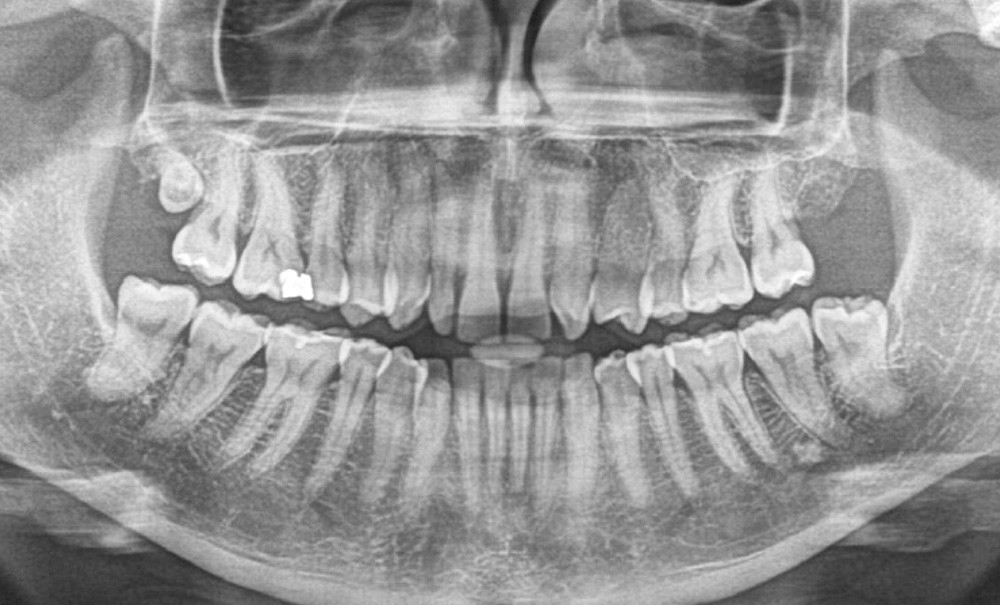

Information dentaire

Les solutions au problème posé par les anomalies de nombre du secteur antérieur sont données par la synthèse de trois groupes de paramètres : paramètres liés au patient, paramètres liés au chirurgien-dentiste, paramètres liés à l’orthodontiste. Quand la solution choisie par le responsable décisionnaire du patient ou le patient lui-même est la réouverture de l’espace d’agénésies, une préparation orthodontique rigoureuse des secteurs impliqués dans le traitement et destinés à recevoir des implants permet de rendre optimale leur intégration tissulaire. Le CBCT est actuellement l’outil radiologique qui permet de répondre aux exigences de l’orthodontiste et du chirurgien-dentiste.

Les agénésies sont un motif de consultation fréquent des patients avec une prévalence de 4,6 % pour les hommes et de 6,3 % pour les femmes en Europe [1]. L’agénésie de l’incisive latérale représente 25 % des agénésies en général, soit 1,5 % sur l’ensemble de la population. La résolution revêt un caractère esthétique et fonctionnel particulier : sourire et guide antérieur sont affectés et nécessitent d’être restaurés. Le diagnostic est aisé. Peu d’erreurs sont possibles.